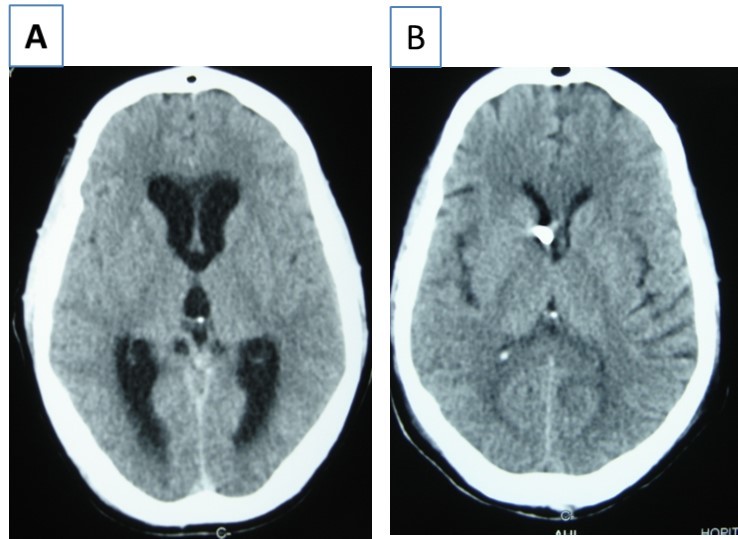

Patient was placed on intra veinous amphotéricin B but this was complicated with acute active hydrocephalus warranting external ventricular drainage (Figure 3). Subsequently, he developped staphylococcal meningitis as day 8 post op, treated with intra veinous vancomycin. Patient developed renal insufficiency and hyperosmolar non ketotic coma for an unknown diabetis for which amphotéricine B therapy was stopped. His neurological status deteriorated with a Glasgow coma scale (GCS)7/15. Posterior fossa surgery was performed with excision of the fungal abscess (Figure 4) and Voriconazol was instituded post operatively for fungal therapy with improvement of the neurological status to GCS 13/15. But the patient succumbed to acute cardiac failure.

Figure 3.cerebral CT scan with axial view showing acute hydrocephalus (A) and control after external ventricular drainage (B)